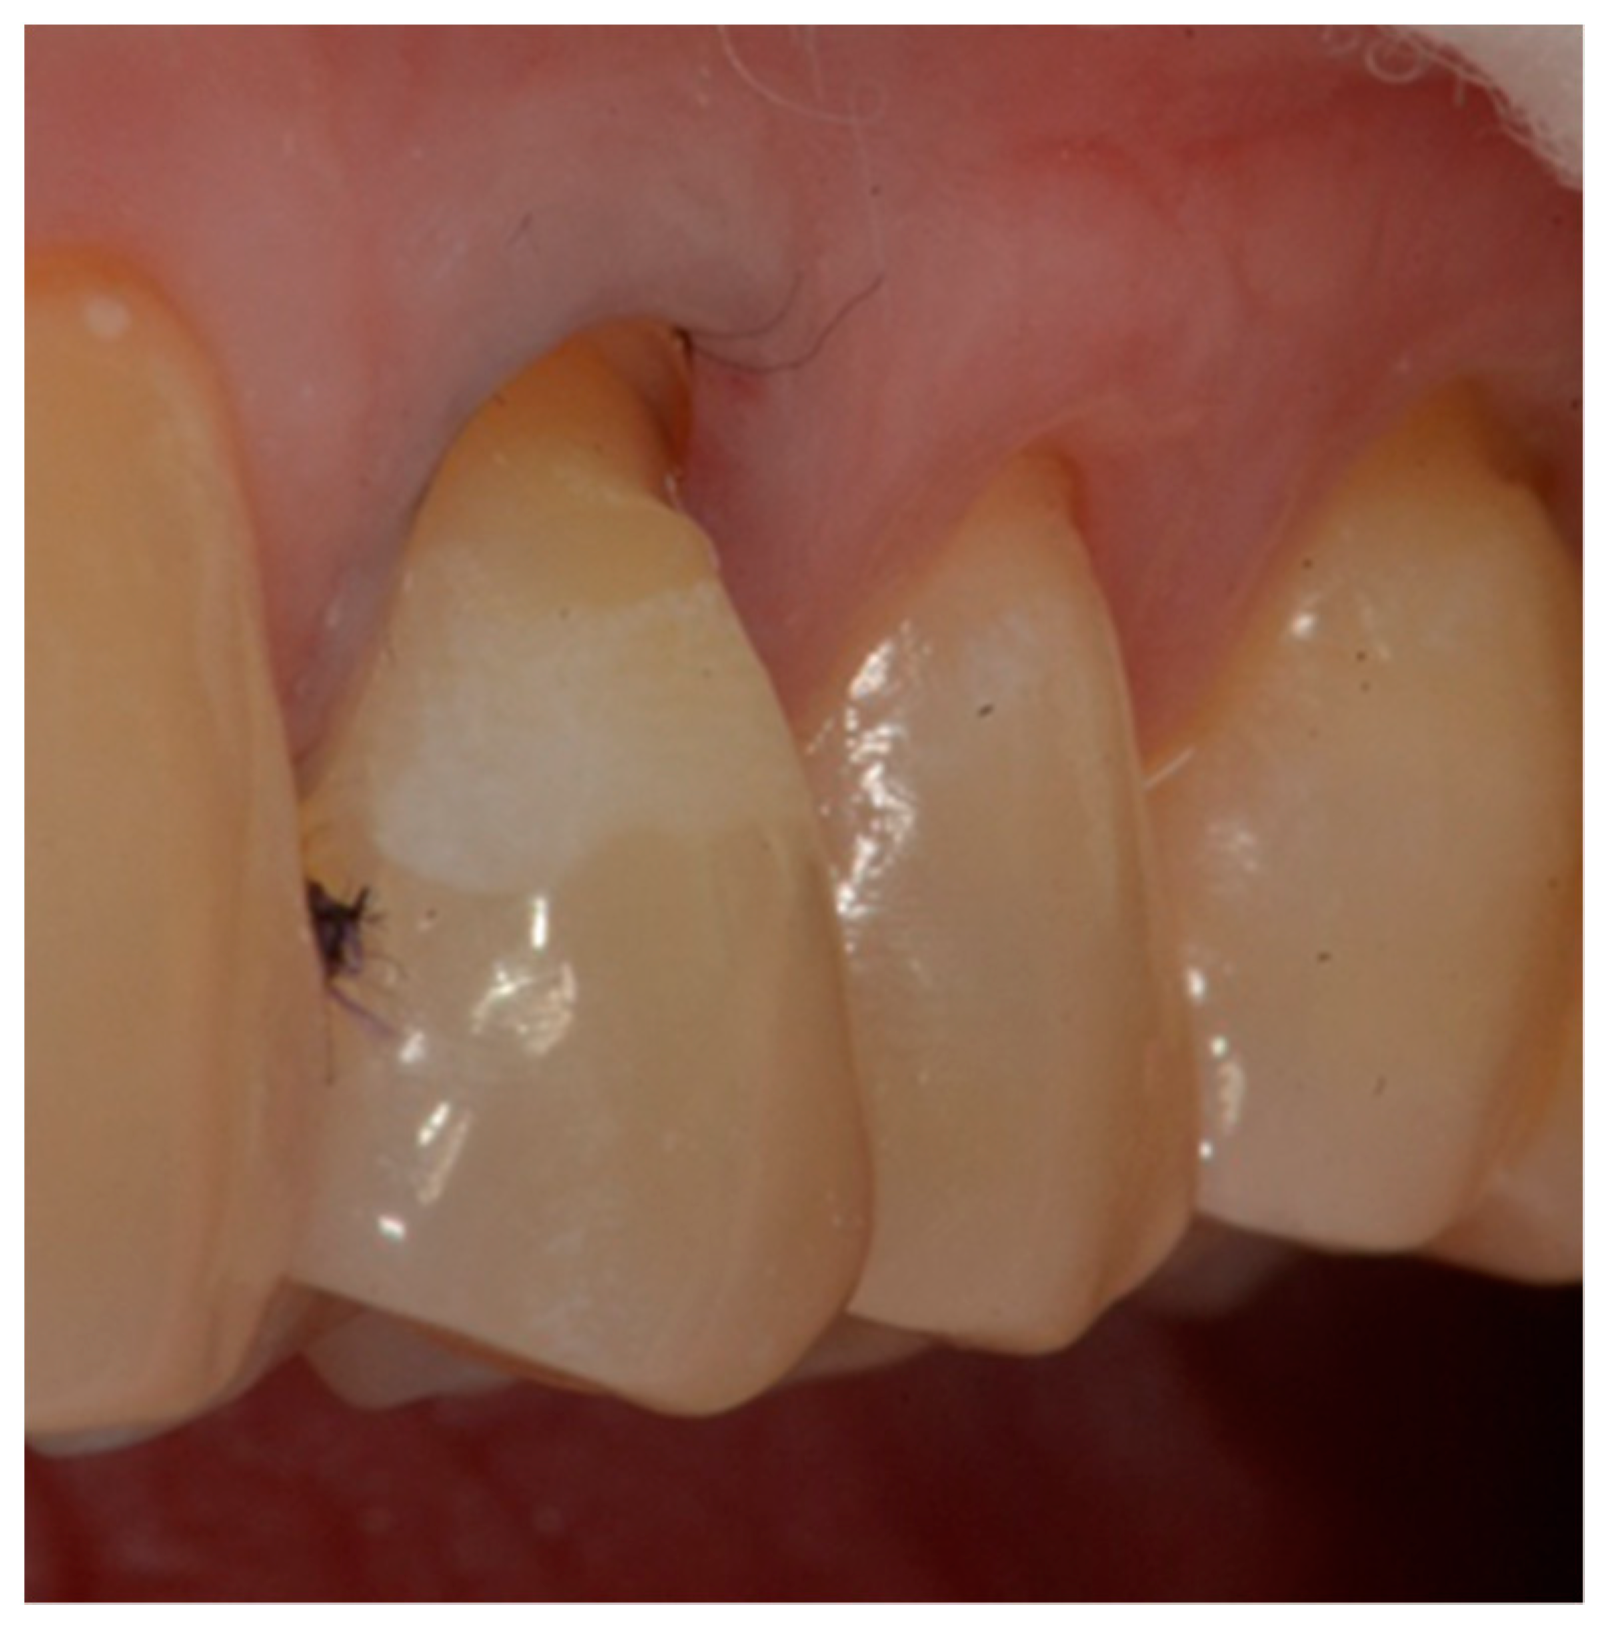

- definition of a small bevel of the enamel (mini-chamfer) in correspondence with the coronal perimeter of the lesion with fine-grained diamond burs to favor the adhesion processes and the mimicry of the restoration and to give sufficient thickness to the most coronal composite (Figure 4).

- First refinement of the restoration and removal of the retraction cord (Figure 7).

- Finishing the restoration with a coarse- (80 μm) and a fine- (50 μm) grain flame bur placed on the most apical point of the restoration, without touching the dental tissue with the tip, in order to create an angle of approximately 45° and maintain a convex profile (Figure 8).